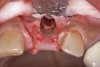

Because the osteotomy created by the trephine is wider than the originally placed implant, it may be challenging to immediately replace this implant unless there is sufficient apical bone available for implant stabilization. For some cases, a wider implant can be placed, but the physiologic rules requiring 1.5 to 2.0 mm for tooth/implant or 3.0 mm for implant/implant spacing,2 as well as other established esthetic criteria, must be respected. For example, a clinical examination revealed a fractured implant in the position of tooth No. 14 along with a fracture to tooth No. 13 (Figure 4). After trephine removal of the fractured implant and extraction of the fractured bicuspid, two implants were placed (Astra Tech, Dentsply Sirona), utilizing apical and axial bone in the apical third of the osteotomy and alveolus to stabilize both fixtures (Figure 5). When this cannot be performed, a staged approach should be employed wherein the site is augmented to facilitate implant placement 4 to 6 months after explantation and grafting.

(4.) The implant in the molar position was relatively narrow and failed biomechanically. It was removed with a trephine, and the adjacent fractured bicuspid was also extracted to accommodate an implant. Because sufficient apical bone was present, a wider implant was placed in the molar position. Bone augmentation was performed around both implants.

Figure 4

(5.) The implant in the molar position was relatively narrow and failed biomechanically. It was removed with a trephine, and the adjacent fractured bicuspid was also extracted to accommodate an implant. Because sufficient apical bone was present, a wider implant was placed in the molar position. Bone augmentation was performed around both implants.

Figure 5